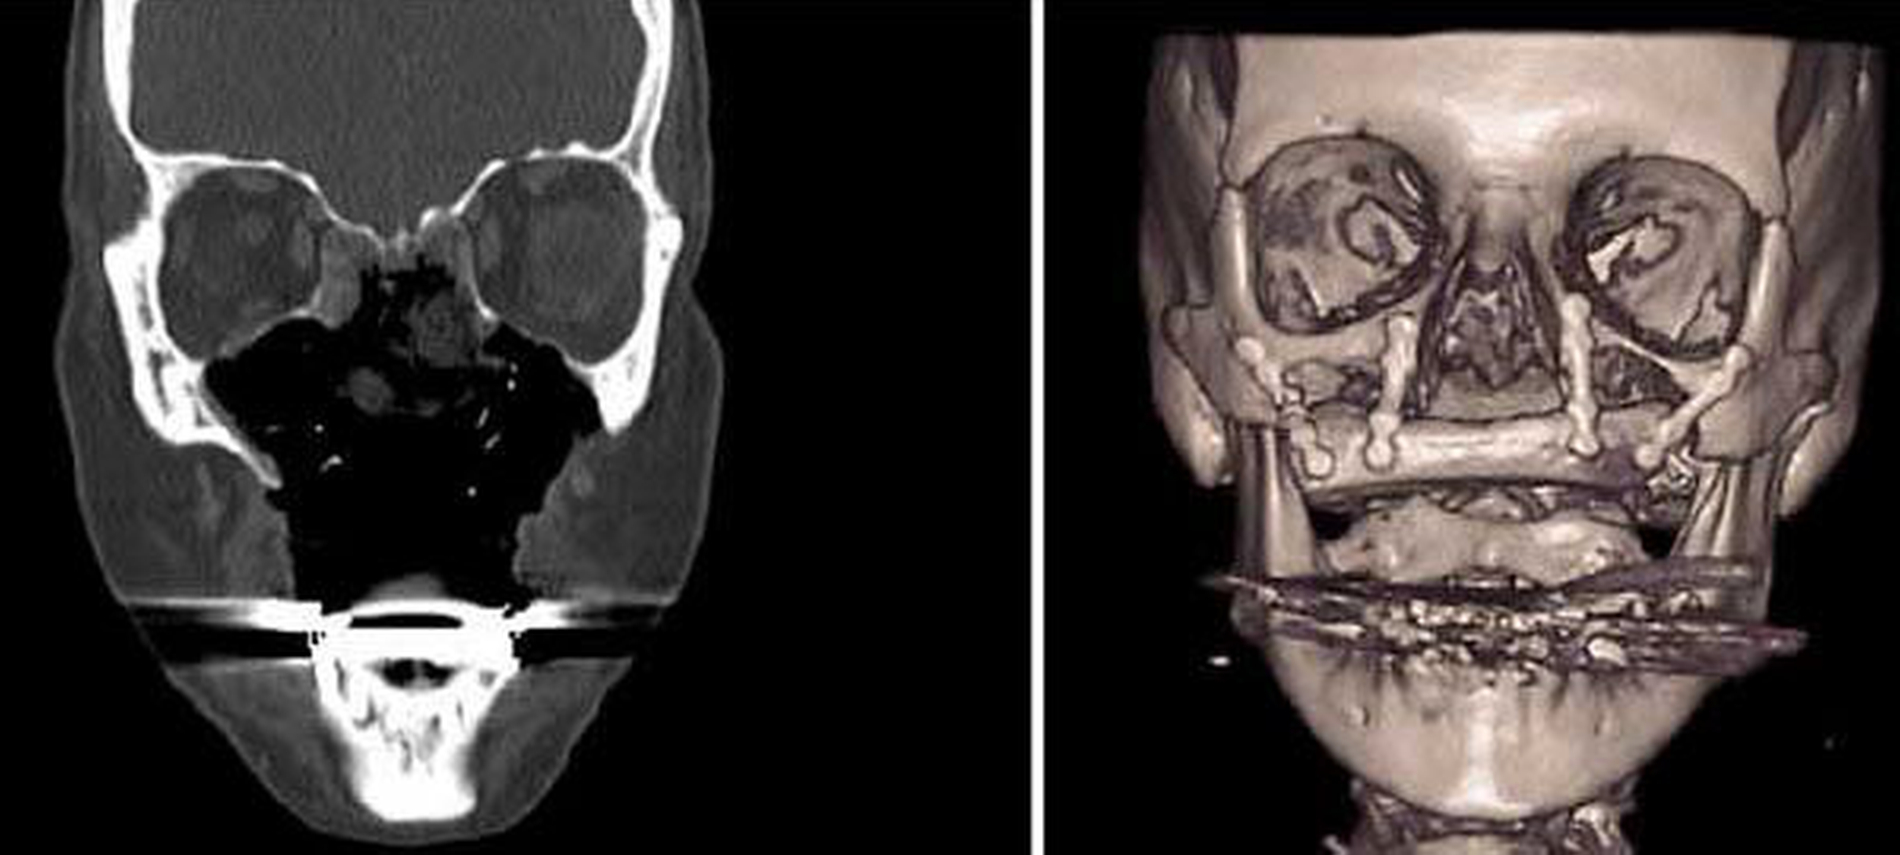

Daraufhin erfolgte die Rekonstruktion des großen maxillären Defekts mittels „Double Flap“-Technik: Für die knöcherne Rekonstruktion wurde ein mikrovaskuläres Beckenkammtransplantat (deep circumflex iliac artery (DCIA)- Flap) von rechts zusammen mit Anteilen des M. obliquus internus entnommen und so im Bereich des Defekts positioniert, dass der Muskelanteil zu den eröffneten Kieferhöhlen und zur Nasenhauthöhle zum Liegen kam. Die osteosynthetische Fixation an den verbliebenen Knochen des Mittelgesichts erfolgte mittels Miniosteosyntheseplatten (Medicon eG, Tuttlingen).

Der Gefäßstiel mit Arterie und Vene des Transplantats wurde intraoral nach Freipräparation an die Fazialisgefäße im Planum buccale anastomosiert (Abbildung 3) angeschlossen.

Während der Operation erfolgte auch die weichgewebliche Rekonstruktion des Vestibulums und des Gaumens mit intraoraler Abdeckung des Beckenkammtransplantats mittels eines freien fasziokutanen Radialistransplantats vom Unterarm links und die Mikroanastomose der Radialisgefäße an die Fazialisgefäße der rechten Seite. Der weitere postoperative Verlauf war komplikationslos. Die Patientin war nach insgesamt sechs Wochen schluckfähig und konnte verständlich sprechen.